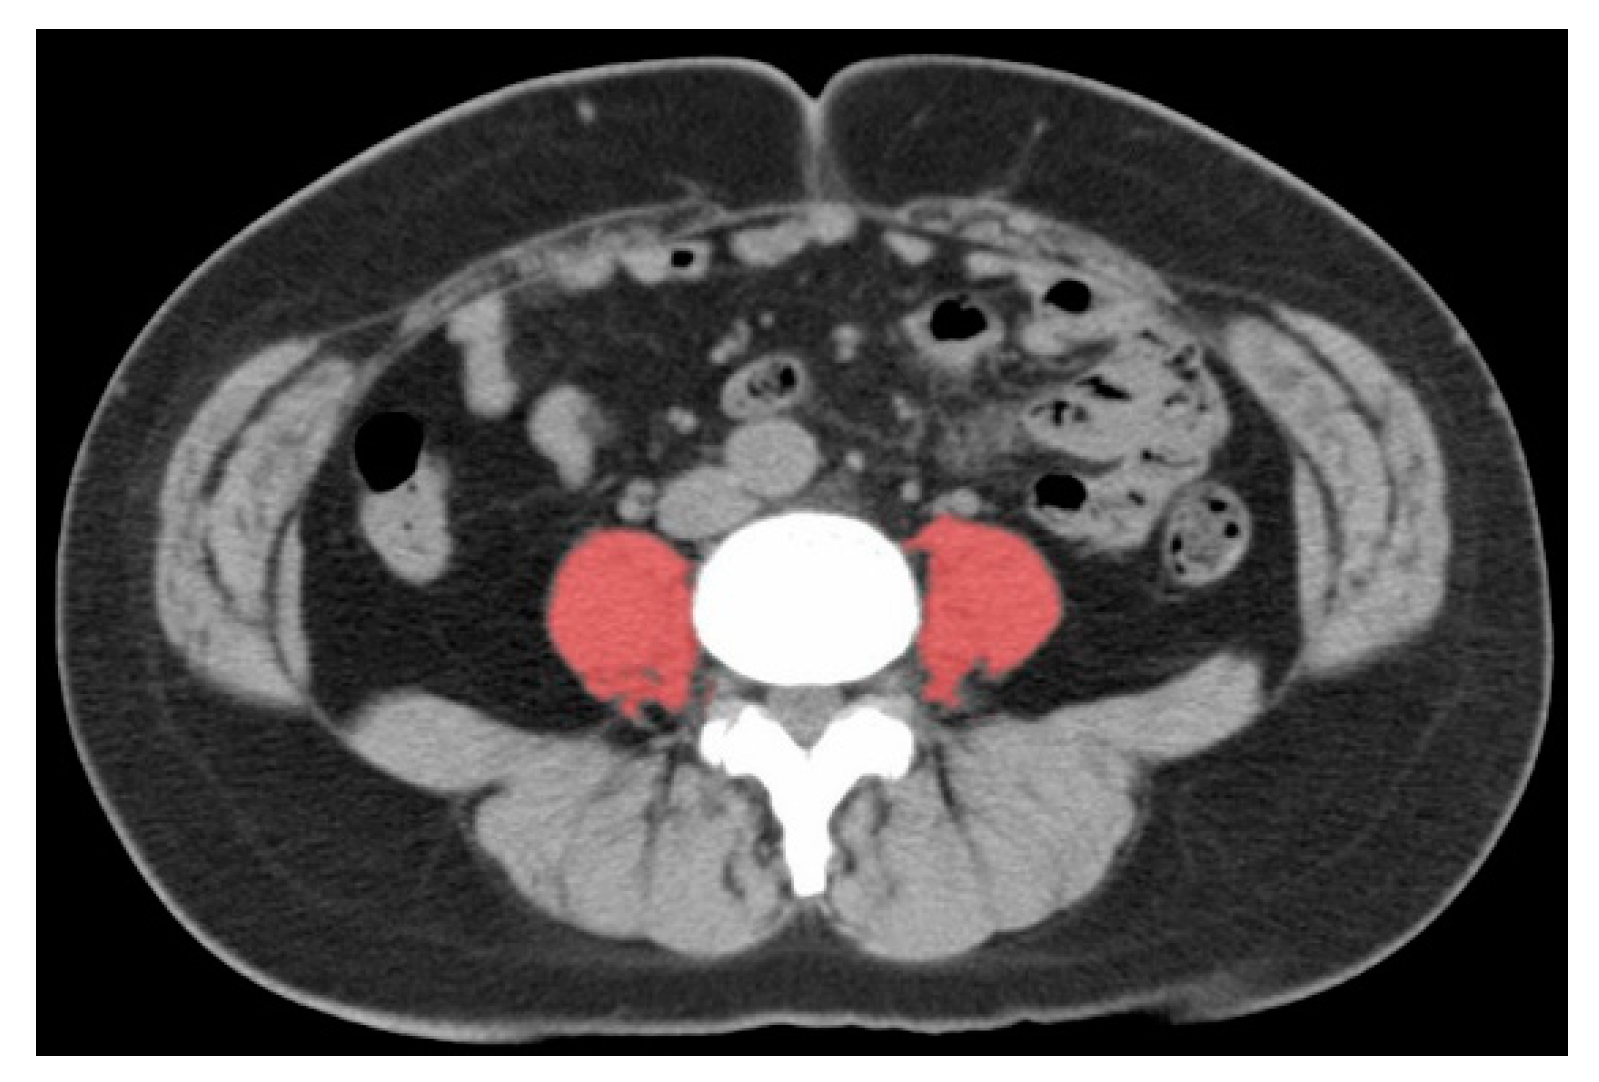

4.5. Skeletal Muscle Assessment

- Hamaguchi, Y.; Kaido, T.; Okumura, S.; Kobayashi, A.; Hammad, A.; Tamai, Y.; Inagaki, N.; Uemoto, S. Proposal for new diagnostic criteria for low skeletal muscle mass based on computed tomography imaging in Asian adults. Nutrition 2016, 32, 1200–1205. [Google Scholar] [CrossRef] [PubMed]